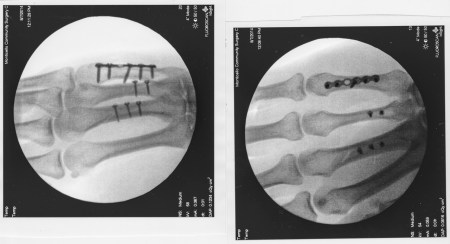

Posted in 5DMII, Astrophotography, Long exposures on August 30, 2014 by budbranch“Gentlemen, we can rebuild him – we have the technology!”